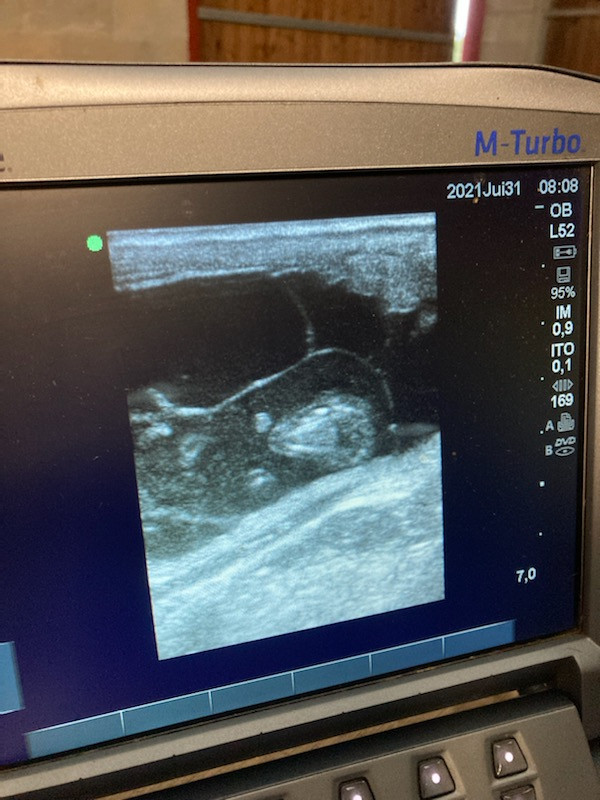

la jument va bien ? Tu as raison de relativiser, bien que je te comprend quand on place tout nos espoirs dans un poulain, le perdre est difficile